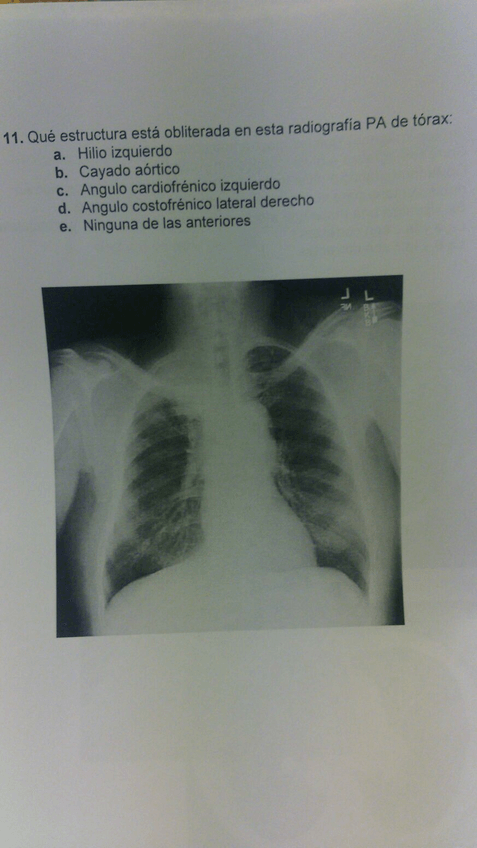

Exámenes Radiología I

He publicado nuevos examenes de 3º radiología clínica y diagnóstico por la imagen: Exámenes Radiología I

Examen-CUD.pdf

Examen-extraordinario-radiologia-07-2020.pdf